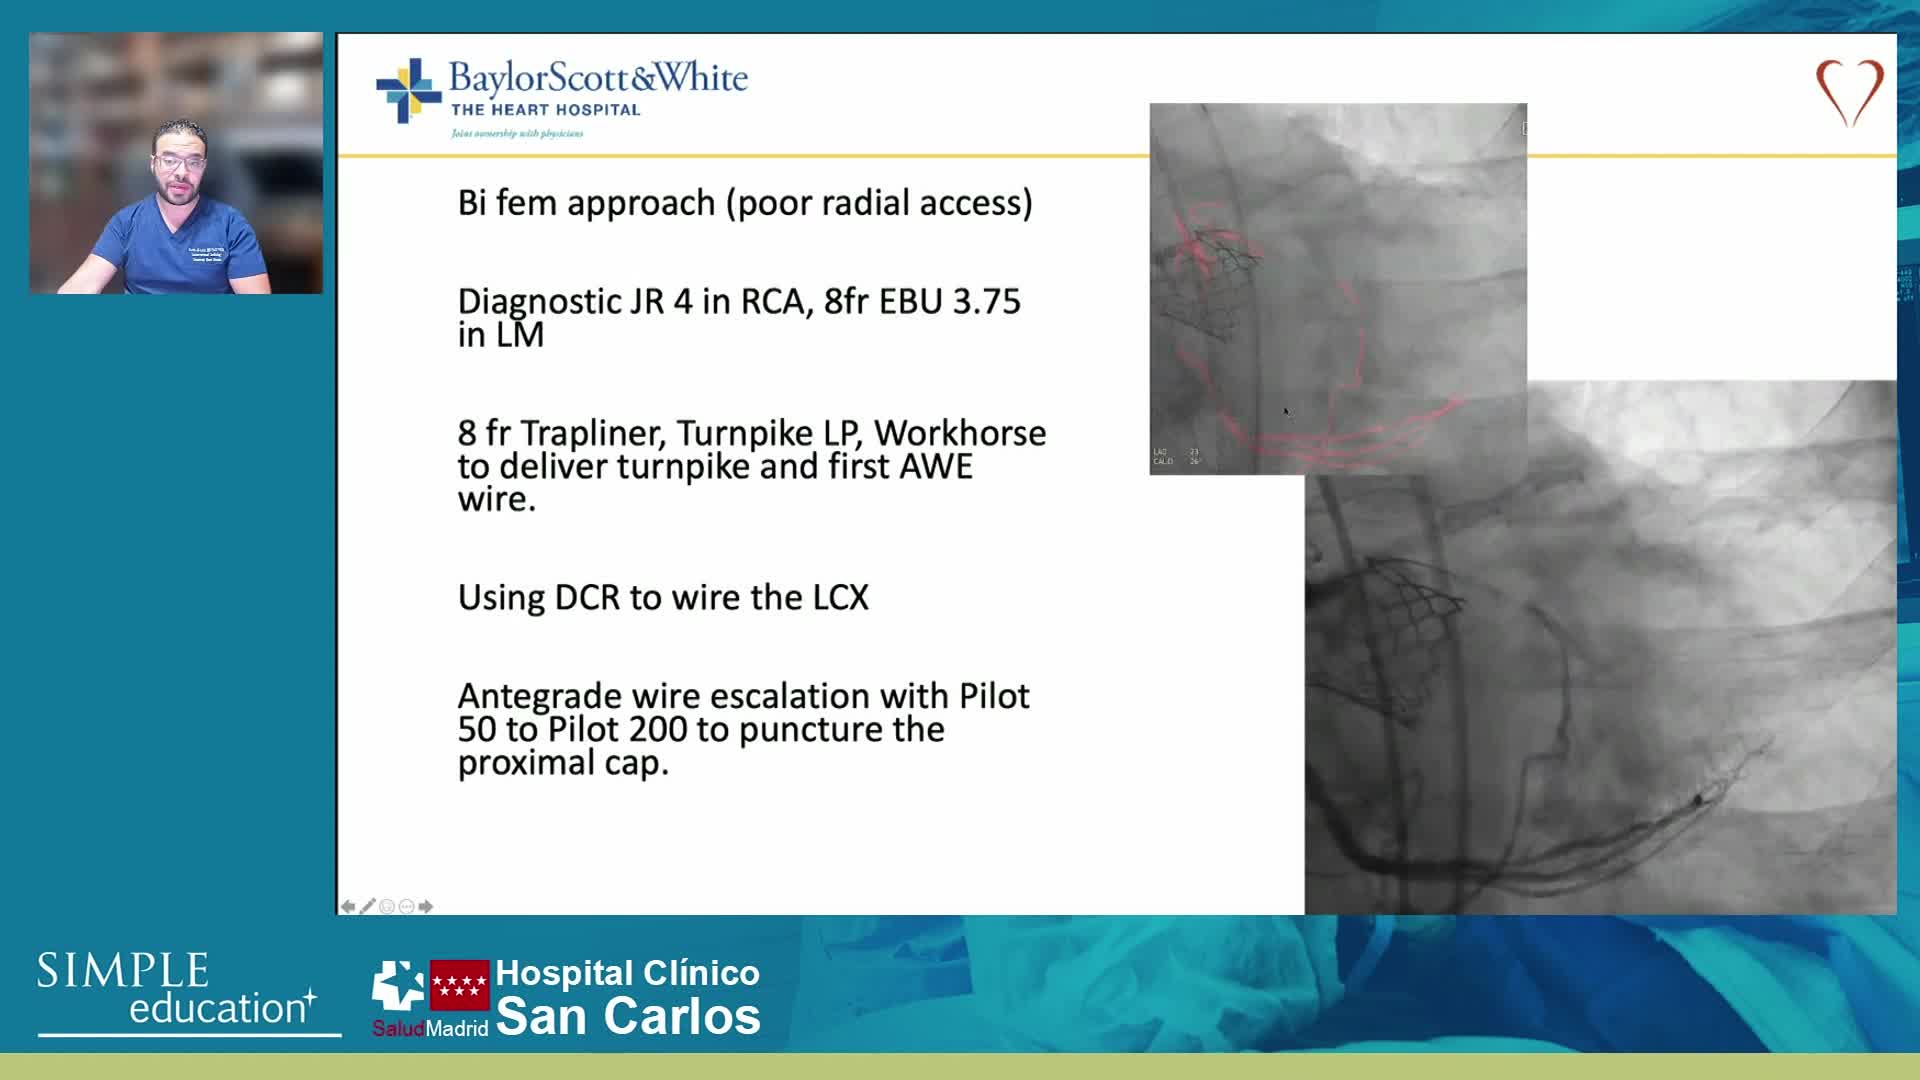

Ultralow Contrast PCI in complex and high risk patients - April 2024 Day One

Ultralow Contrast PCI in complex and high risk patients - April 2024 Day Two

Ultralow Contrast PCI in complex and high risk patients - November 2023 Day One

Ultralow Contrast PCI in complex and high risk patients - November 2023 Day Two